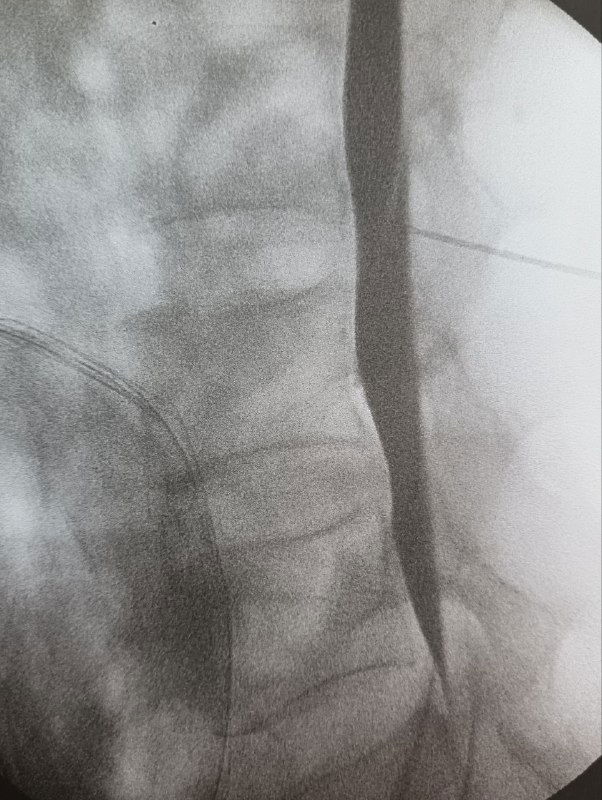

Полгода назад выполнял миелографию.

Процедура редкая — сегодня к ней прибегают нечасто, поскольку МРТ давно вытеснило большинство инвазивных методов.

Нужно было исключить синдром ликворной утечки.

МРТ — без патологии.

Миелография — тоже ничего не показала.